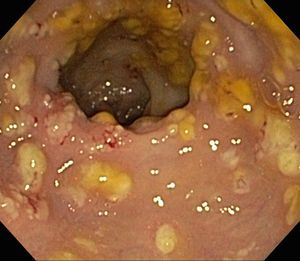

''C. difficile'' 독소를 검출하는 검사가 나오기 전에는, 결장경 검사나 S상 결장경 검사를 통해 진단하는 경우가 많았다. 결장 또는 직장 점막에서 "가성 막"의 출현은 이 질환을 시사하지만, 진단적인 것은 아니다.[46] 가성 막은 염증성 잔해물과 백혈구로 구성된 삼출물로 이루어져 있다. 현재도 결장경 검사 및 S상 결장경 검사가 사용되기는 하지만, 현재는 ''C. difficile'' 독소 존재 여부를 검사하는 대변 검사가 진단의 첫 번째 단계로 자주 사용된다. 일반적으로 독소 A와 독소 B 두 가지만 검사하지만, 이 균은 다른 독소도 여러 개 생성한다. 이 검사는 100% 정확하지 않으며, 반복 검사에도 위음성률이 상당하다.[47]

가성 막성 대장염은 1978년, ''C. difficile'' 감염의 합병증으로 처음 기술되었으며, 가성 막성 대장염 환자로부터 독소가 분리되고 코흐의 가설이 충족되었다.[220]